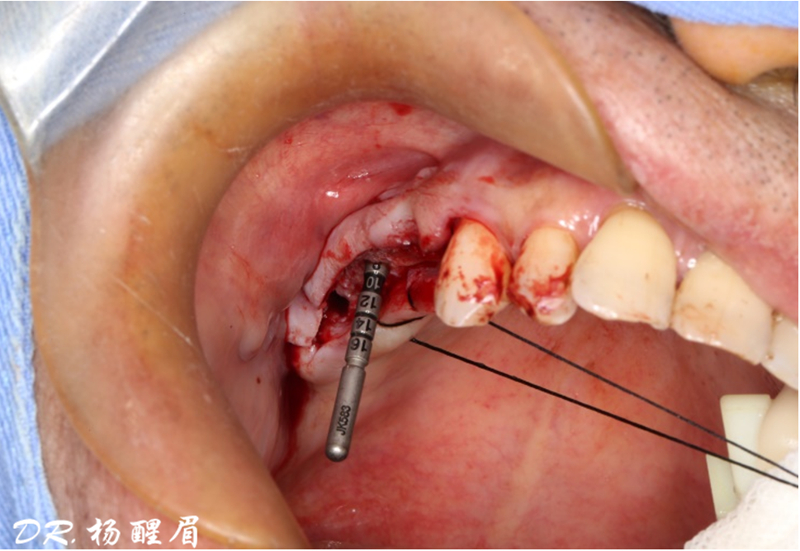

®完成標定及配準

®按照術前方案進行備洞及植體植入

®按照術前方案進行備洞及植體植入,醫(yī)生可以通過屏幕軟件引導對手術中植入點、角度、深度實時追蹤

®對植體深度及方向進行確認

®完成3顆植體的植入,植體位點如術前方案設計,均在同軸線。